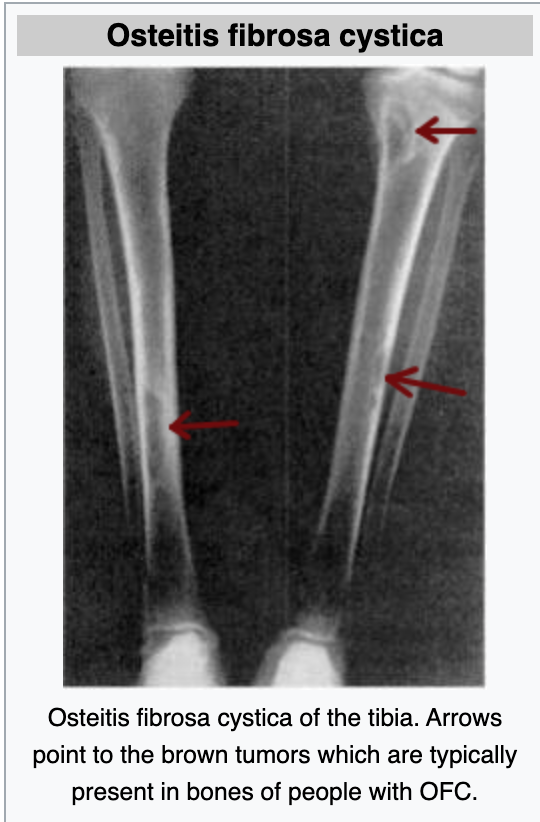

What is Osteitis Fibrosa?

1. give the features

2. Give symptoms

Features:

* loss of bone mass

* weakening of bones and calcified structures - this is replaced with fibrous tissue (peritrabecular fibrosis)

* formation of small cyst-like brown tumours

Symptoms:

* Bone pain

* tenderness

* fractures

* skeletal deformities